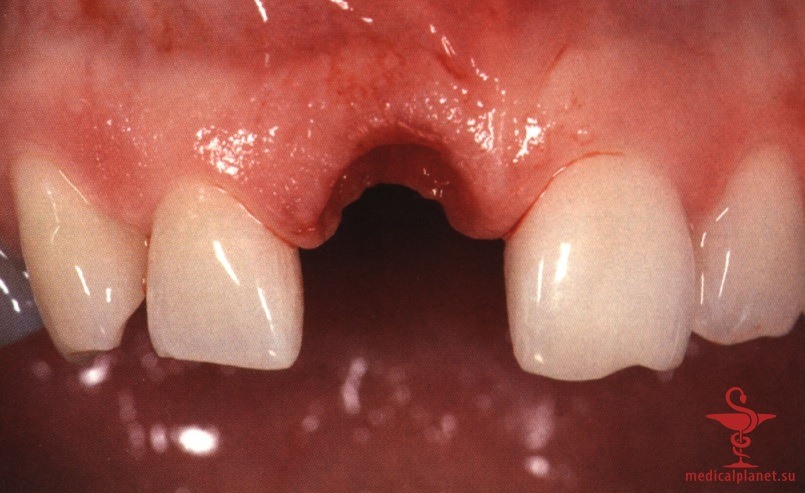

Следует помнить, что любой, даже самый маленький лоскут требует наложения швов в области сосочков, а каждый разрез в этой зоне ведет к уменьшению их высоты, как обсуждалось в отдельной статье на сайте (просим Вас пользоваться формой поиска по сайту выше) (рис. 3). Иными словами, при немедленной имплантации в эстетически значимой зоне нужно избегать отслаивания лоскута.